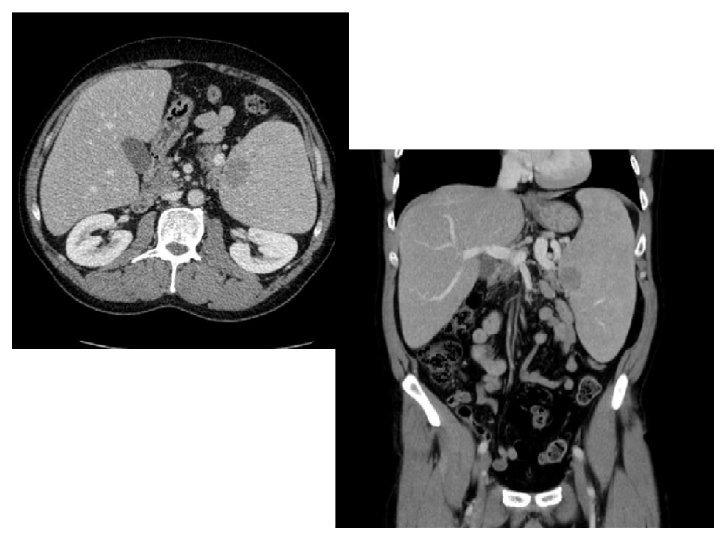

Niemann Pick type B • Initial presentation – Spleen 78% – Liver 73% • Symptoms – Bleeding 49% – Pulmonary infections 42% – Shortness of breath 42% – Joint/limb pain : 39% Mc. Govern MM, et al. Paediatrics 2008.

Phase 2 – Endpoints • Primary Efficacy Endpoint - % reduction in spleen volume (MN) by MRI – 15 patient Trial (5 per arm) is powered (>90%) to detect a clinically meaningful reduction in spleen volume (>20%) and dose responsiveness (linear trend test by ANOVA) – Assumptions - spleen volume reductions of 30, 45, and 60% (0. 3, 1, and 3 mg/kg), standard deviation 10%, 15% dropouts, two-sided p<0. 05 • Secondary Endpoints – Liver volume - MRI – Pulmonary imaging – CXR, HRCT – Pulmonary function tests - % predicted DLco/FVC/FEV 1/TV – Exercise capacity by cycle ergometry - % predicted maximum workload, O 2 consumption, and CO 2 production – Physician global assessment – Efficacy biomarker – chitotriosidase – Hematology – platelet count, hemoglobin, WBC

Phase 2 : inclusion • • • Plus de 18 ans Déficit en sphingomyélinase acide 20 < patient >= 80% DLCO Rate > 6 N – splénectomie partielle Test grossesse négatif Contraception efficace